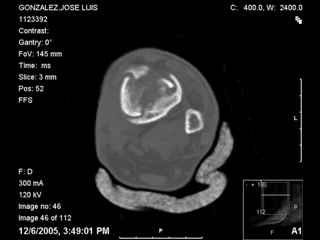

A 56 year old laborer fell off a wall approximately 5 months ago. He sustained an open pilon fracture. He was treated with debridement and external fixation. After he was treated for 4 months, the external fixator was removed.

The patient had no medical insurance and was therefore transferred to my care by his treating surgeon. He has remained NWB. He denies pain in his ankle. He has painless dorsiflexion and plantarflexion of his ankle joint.

I have attached his x-rays. I have also attached an WMV movie file of his axial CT (if you are unable to view this, I can post an MPEG file).